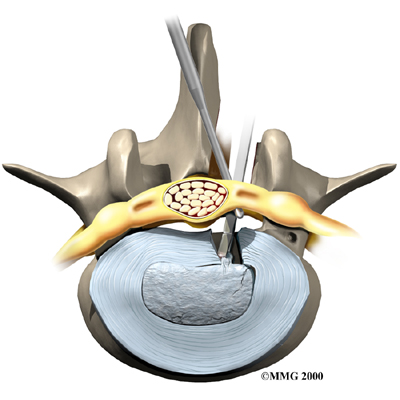

Microdiscectomy

Microdiscectomy is becoming the standard surgery for lumbar disc herniation. The procedure is used when a herniated disc is putting pressure on a nerve root. It involves carefully taking out part of the problem disc (discectomy). By performing the operation with a surgical microscope, the surgeon only needs to make a very small incision in the low back. Categorized as minimally invasive surgery, this surgery is thought to be less taxing on patients. Advocates also believe that this type of surgery is easier to perform, that it prevents scarring around the nerves and joints, and that it helps patients recover more quickly.

Related Document: FYZICAL South San Antonio's Guide to Lumbar Discectomy